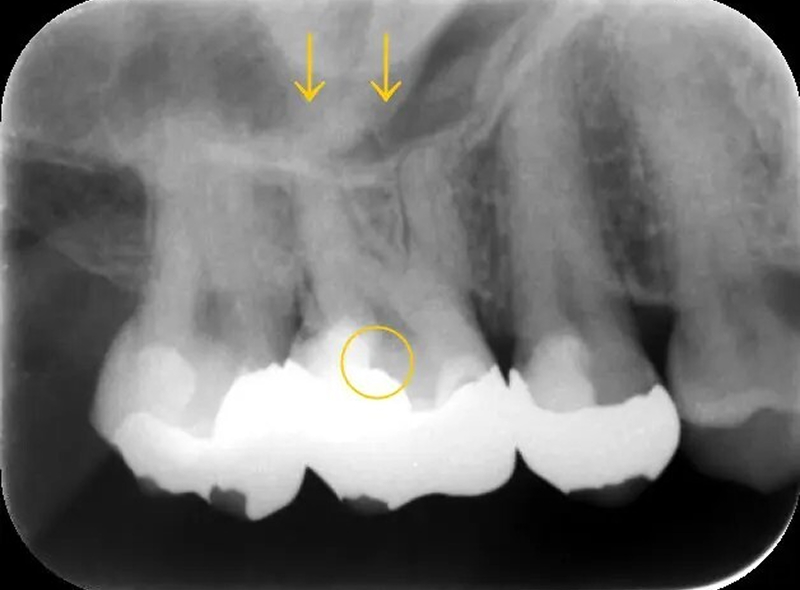

1年半前に保険治療で入れた右上の銀歯に違和感が続き、「歯髄(神経)を取る必要がある」と診断された患者様が、質の高い治療を求めて来院されました。

レントゲンで診ると、歯髄の近くまで歯を削っていることがわかります。

感染部分を取ると歯髄が露出しましたが、腐敗していない為、歯髄温存療法を行いました。

もともとあった違和感は治療後すぐに無くなり、経過良好です。